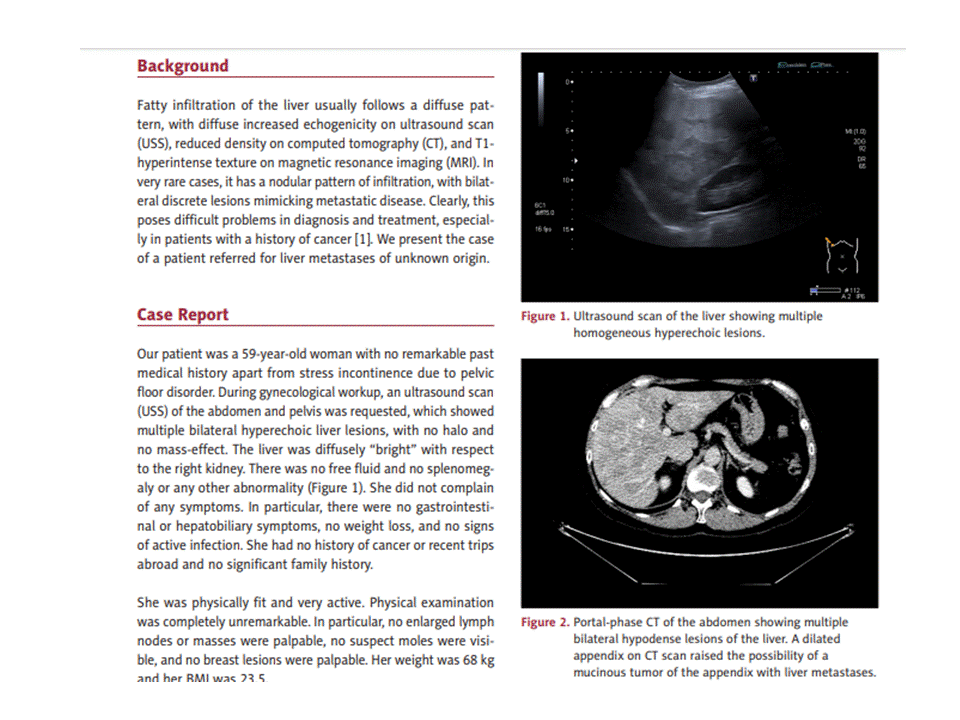

UNUSUAL NODULAR FATTY INFILTRATION of the LIVER